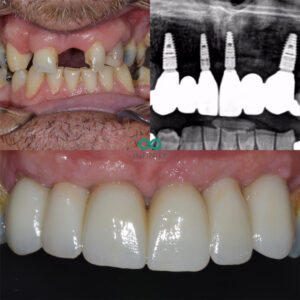

In this blog I will take you through the stages of how we replaced the front 6 failing/ missing teeth for this patient using 4 dental implants and 6 implant supported teeth.

The front six (anterior) were replaced with 4 dental implants that were strategically placed in the Upper right canine, upper right cental incisor, upper left central incisor and upper left canine regions. This would allow us to fit 6 replacement teeth onto the 4 dental implants whilst still maintaining the ‘individual’ look of the 6 teeth when completed. In this case we opted to place 4 dental implants rather than 6 individual dental implants. The reasons for this were firstly to preserve bone integrity. By only placing 4 dental implants we are able to preserve more bone between the dental implants that will prove vital for long term ridge strength and stability. Another benefit of only using 4 dental implants is that we can ‘splint’ the implants together in the form of a ‘bridge’. This provides a bracing effect which enhances the strength of the replacement teeth and implants significantly in the long term.

The dental implant placements were carefully planned and placed using the CBCT radiograph. The CT scan enables our team to make every surgery safe and maximise the anatomy of each patient to place the dental implants in the optimum position. This is key to providing natural looking teeth that stand the test of time! We also provided bone grafting and gum grafting during the implant surgery to enahce the volume and strength of the bone and gums which are vital for long term success.